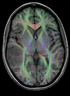

| 3 | brain | tumor | nonrigid | Fast Nonrigid BSpline | DTI | align DTI volume with structural reference scan (T2) | 4.1 | RegLib_C03.mrb: raw data only, use this to run the tutorial from the start (Slicer mrb file. 75 MB). | |

| 29 | brain | tumor | 12 + nonrigid | General Registration (BRAINS) | DTI | Alignment of DTI scan to structural reference T2/T1-SPGR for surgical planning (tumor resection) | 4.2 | RegLib_C29.mrb (130MB, incl. solutions) RegLib_C29_raw.mrb: raw data only |